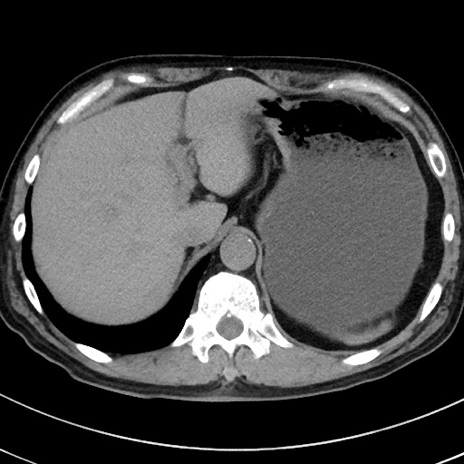

症例38(横断像)

【症例】70歳代 男性

【主訴】腹痛・嘔吐

【現病歴】昨晩より、嘔吐・腹痛あり。今朝になっても嘔吐あり。来院。

【既往歴】心臓バイパス手術、開腹胆摘、腸閉塞

【身体所見】BP 107/71mmHg、HR 116/min、腹部:平坦、軟、下腹部に軽度圧痛あり。反跳痛なし。

【データ】WBC 15100、CRP 0.32